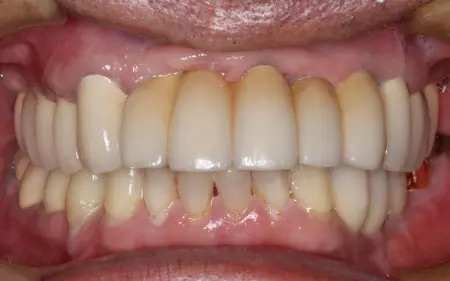

インプラントセラミック

2026.04.0550代男性 欠損していた下左右奥歯にインプラントを埋入してしっかりと噛めるように治療した症例